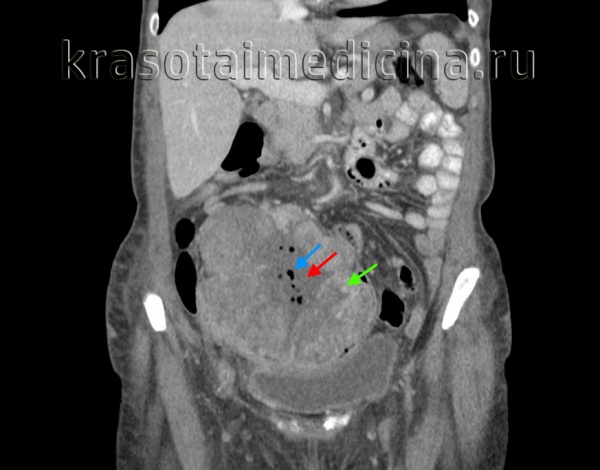

КТ живота и таза. Массивное объемное образование яичника с гиповаскулярным центром (красная стрелка), гиперваскулярной периферией (зеленая стрелка) и включениями газа (синяя стрелка). Гистологически подтвержденная гранулезоклеточная опухоль яичника.